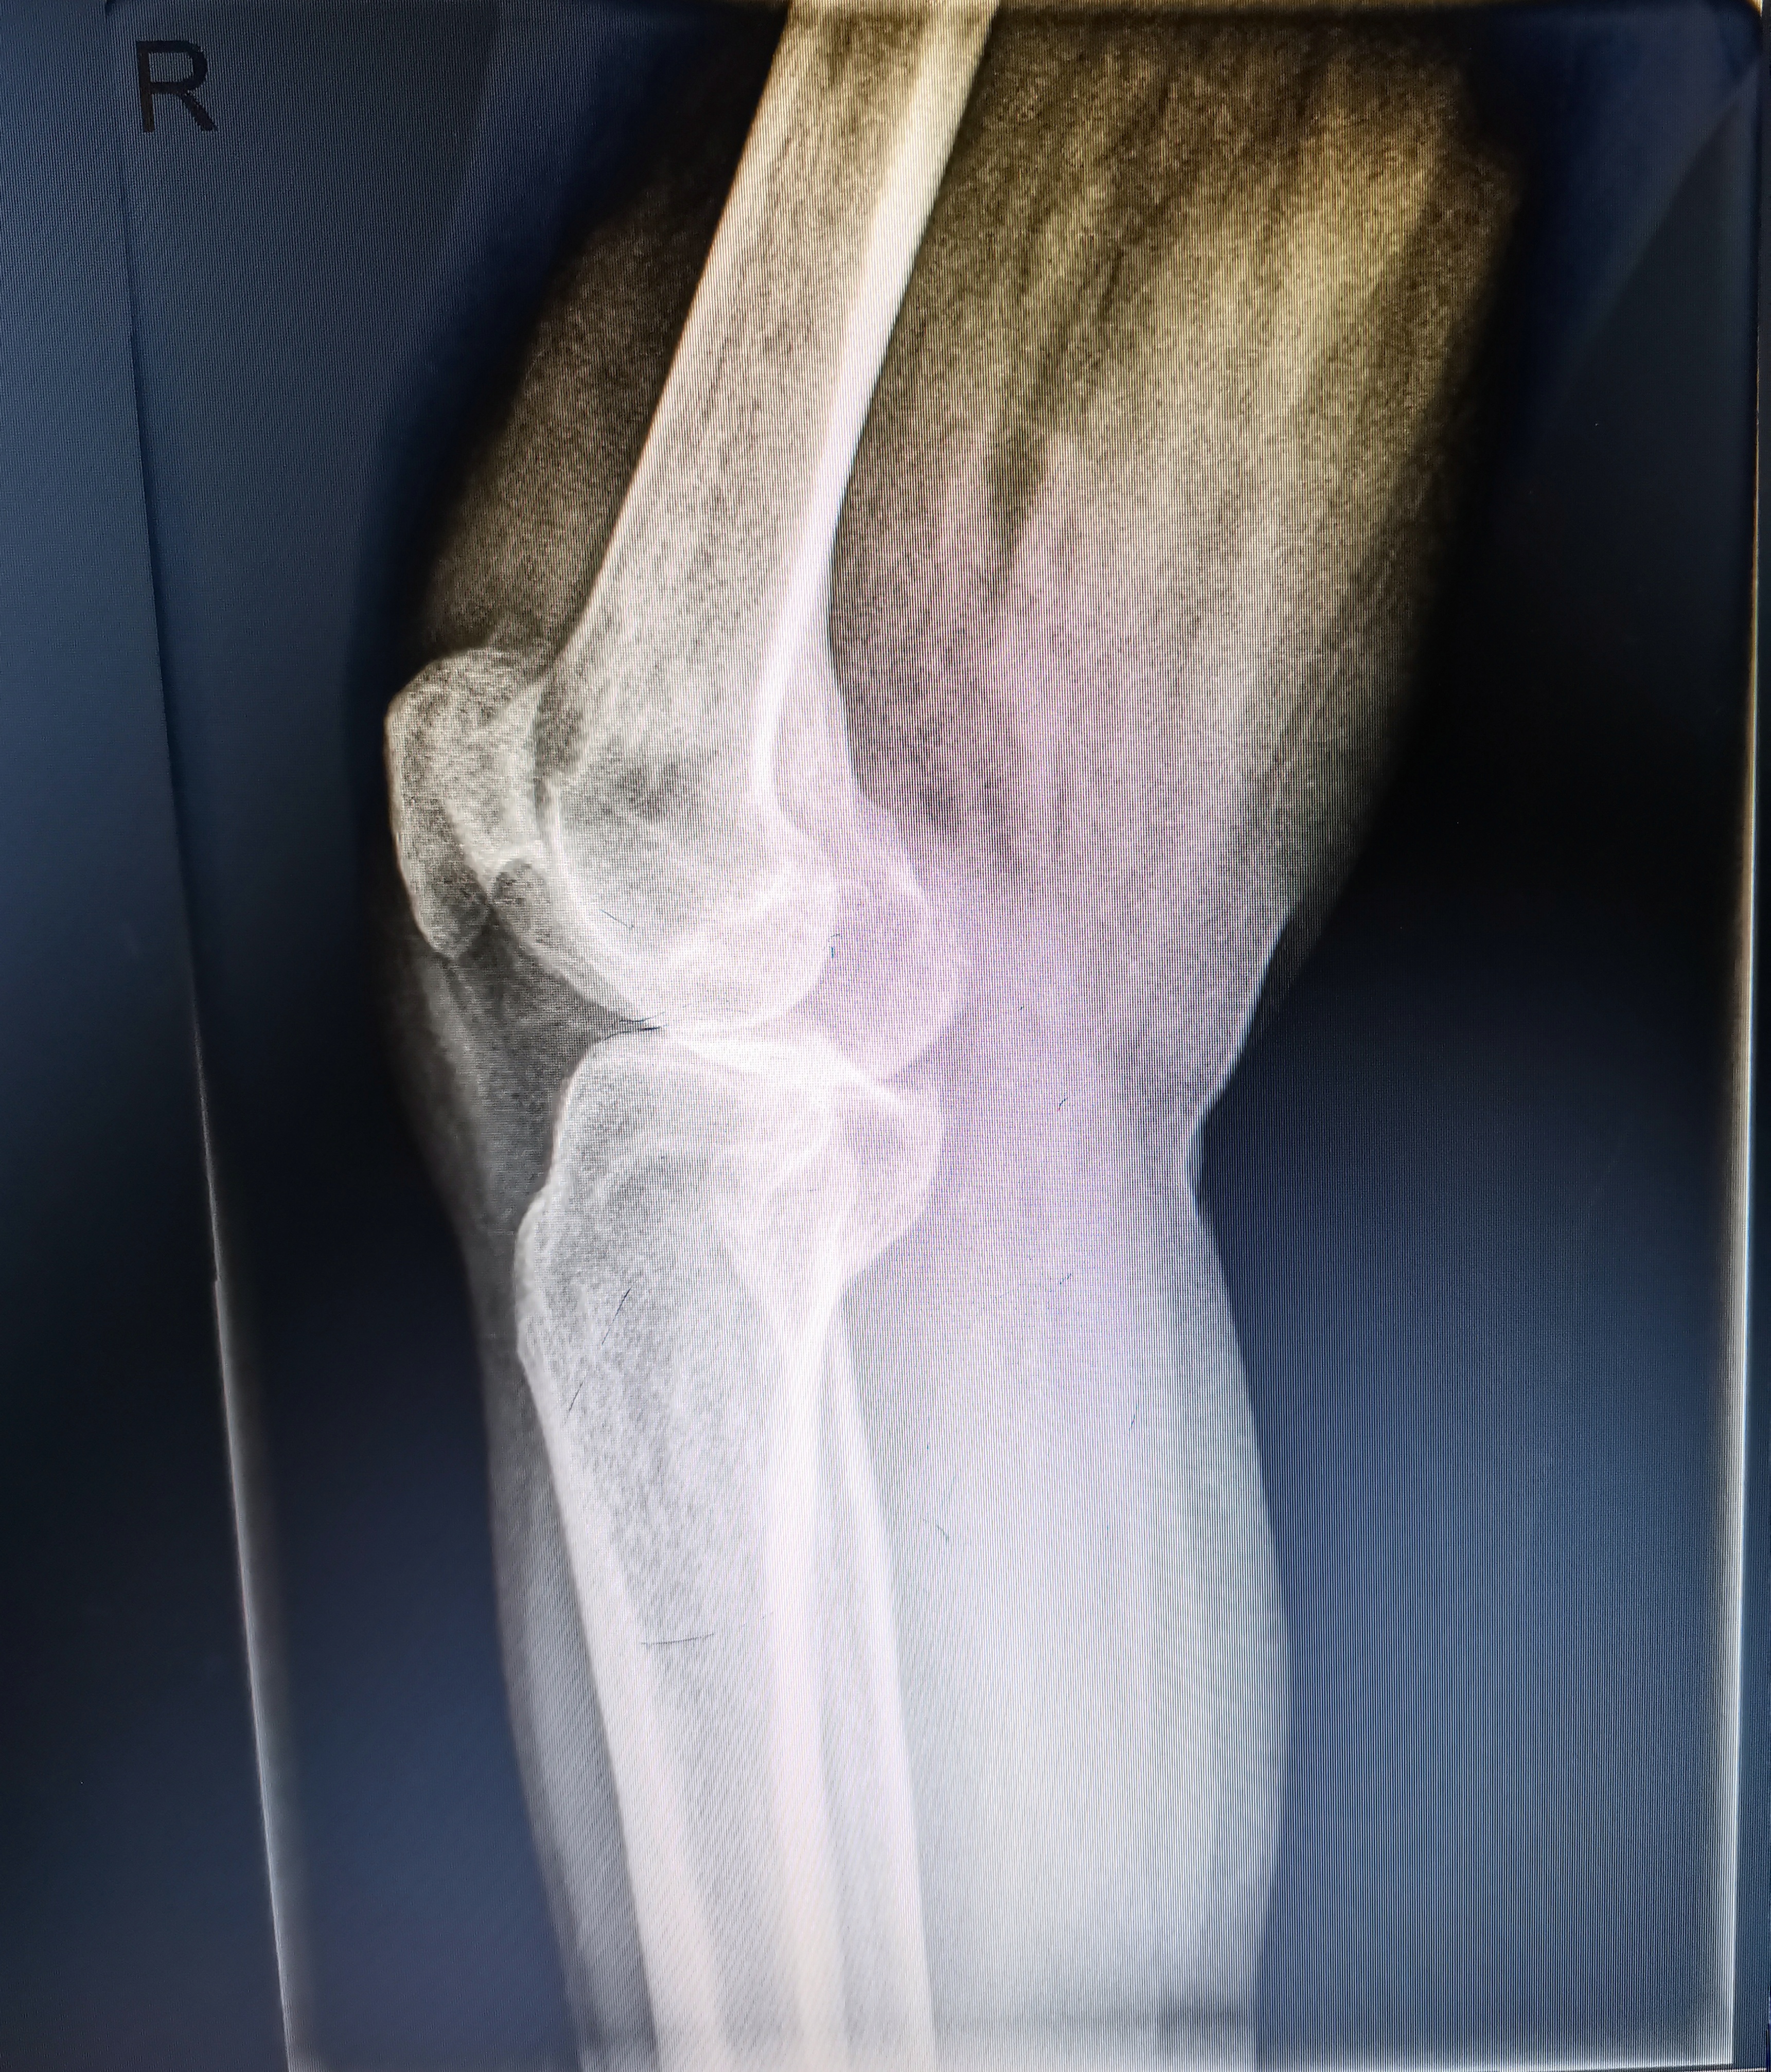

術(shù)前照片